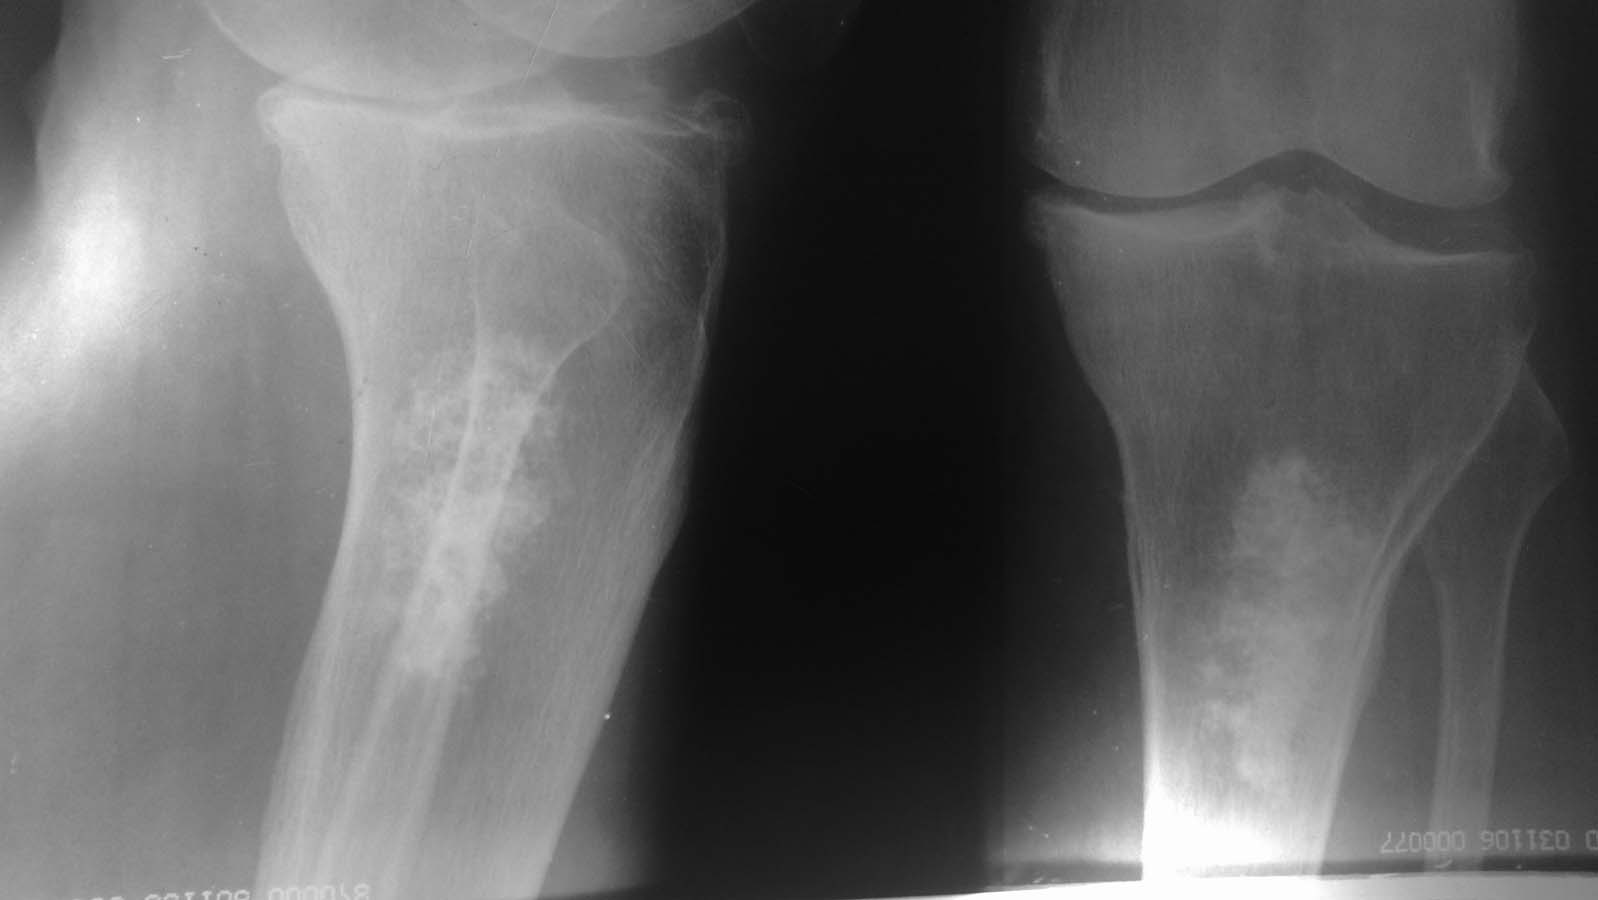

Пациентка 65 лет

что это может быть за образование?

Внутрикостный хондроматоз. Нужна КТ.

При подтверждении - оперативное лечение, удаление хондромных тел, заполенение полости коллапаном, хронос и.т.д.

Если не оперировать может озлокачествляться.

Абсцес Броди

Уважаемый, Анвар! Это может быть остеосаркома.

Возможно,злокачественная опухоль кости,нужна гистология,и в любом случае оперативное удаление

Возможно, это просто обызвествление после инфаркта костного мозга. Клиника в чем состоит?

Это энхондрома. Вероятность преобразования в злокачественную опухоль менее одного процента. Симптомы преобразования, рост опухоли или боль в районе опухоли. У вашей пациентки артрит, так что скорее всего у неё просто болит колено от артрита. Сделайте КТ, а потом проводите рентген контроль, сначала раз в три месяца, потом раз в шесть, а потом ежегодно. Если будет рост опухоли или боли в её районе, повторите КТ, чтобы подтвердить, растёт ли она. А так, её лучше не трогать.

Согласен с Алексеем Николаевичем, это банальный инфаркт костного мозга.